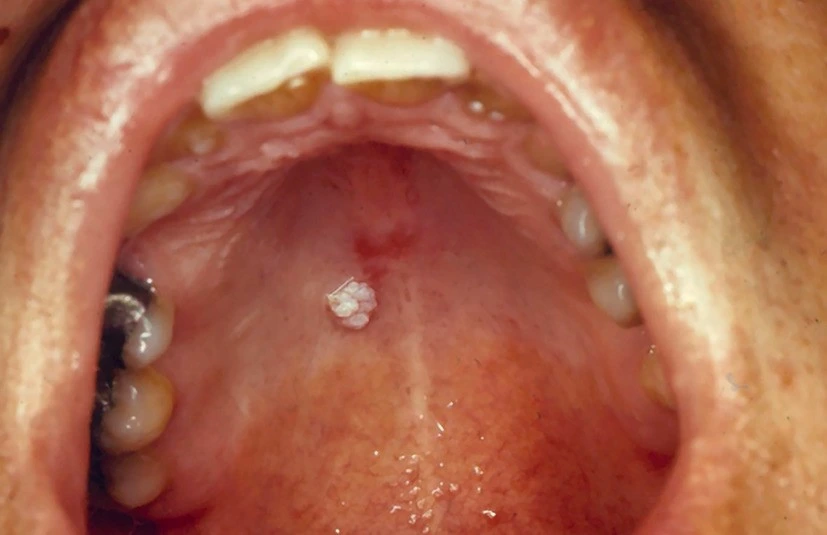

علائم زگیل دهانی

Symptoms of oral warts

برخی اوقات نماهای نرمال دهان مثل جوانه های چشایی زبان با ضایعات اچ پی وی دهانی اشتباه گرفته میشوند. برای تشخیص و اطمینان از ابتلا به اچ پی وی دهانی بهترین گزینه مراجعه به متخصص بیماری های دهان است.

معاینۀ کامل دهان توسط متخصص بیماریهای دهان انجام میشود. درصورت مشاهدۀ ضایعه، برداشت ضایعه توسط لیزر و در برخی مواقع، توسط برش با تیغ و بخیه انجام میشود. ضایعه برای تعیین سروتایپ (نوع ویروس) و همچنین، تشخیص قطعی به پاتولوژی فرستاده میشود. درصورتیکه ضایعه مرتبط با سویههایی با ریسک بالا برای ایجاد سرطانهای دهان (انواع 16 و 18) باشد، بررسی دورهای منظم به بیماران توصیه میشود.